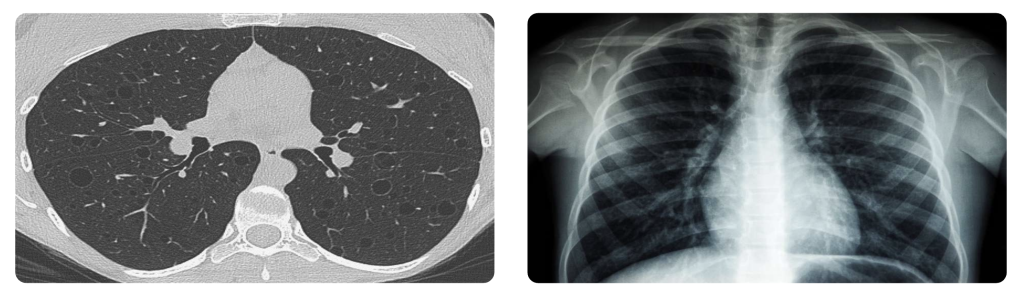

We now know that traditional detection tools like the ILO Chest X-ray, while once sufficient, aren’t sensitive enough to pick up early signs of silicosis or related lung conditions. And in today’s rapidly evolving safety landscape, especially across Australia’s high-risk sectors, that gap carries enormous consequences.

High-Resolution Computed Tomography (HRCT) is helping bridge that gap — not by replacing existing systems overnight, but by providing a clearer, earlier, and more reliable way of seeing what’s happening inside the lungs. For health professionals, regulators, and employers, it’s becoming increasingly clear: if we want to protect lives, we need to see more.

ILO Chest X-rays have been used for decades in worker health monitoring programs but they come with real limitations. The imaging is two-dimensional, and subtle early-stage lung changes, especially in diseases like silicosis, can go undetected. For a worker, this means they may pass their regular screening, only to receive a diagnosis months or years later — when symptoms are harder to treat and damage may be irreversible.

In contrast, HRCT provides a detailed, three-dimensional view of the lungs. It picks up early changes like ground-glass opacities, nodules, and fibrosis long before they appear on a chest X-ray. These findings aren’t just medically important as they empower early intervention, workplace adjustments, and timely treatment.